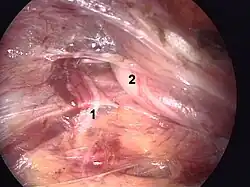

Intraoperative view by TEP Operation. 1. Genital ramus of genitofemoral nerve. 2. Preperitoneal lipom and spermatic cord.

There are two main methods of laparoscopic repair: transabdominal preperitoneal (TAPP) and totally extra-peritoneal (TEP) repair, and these have been demenstrated to yield similar outcomes.[65] When performed by a surgeon experienced in hernia repair, laparoscopic repair causes fewer complications than Lichtenstein, particularly less chronic pain. However, if the surgeon is experienced in general laparoscopic surgery but not in the specific subject of laparoscopic hernia surgery, laparoscopic repair is not advised as it causes more recurrence risk than Lichtenstein while also presenting risks of serious complications, as organ injury. All that said, many surgeons are shifting to using laparoscopic techniques as they require smaller incisions, and result in less bleeding, lower infection rates, faster recovery, shorter hospitalization periods, and reduced chronic pain.[66][67]